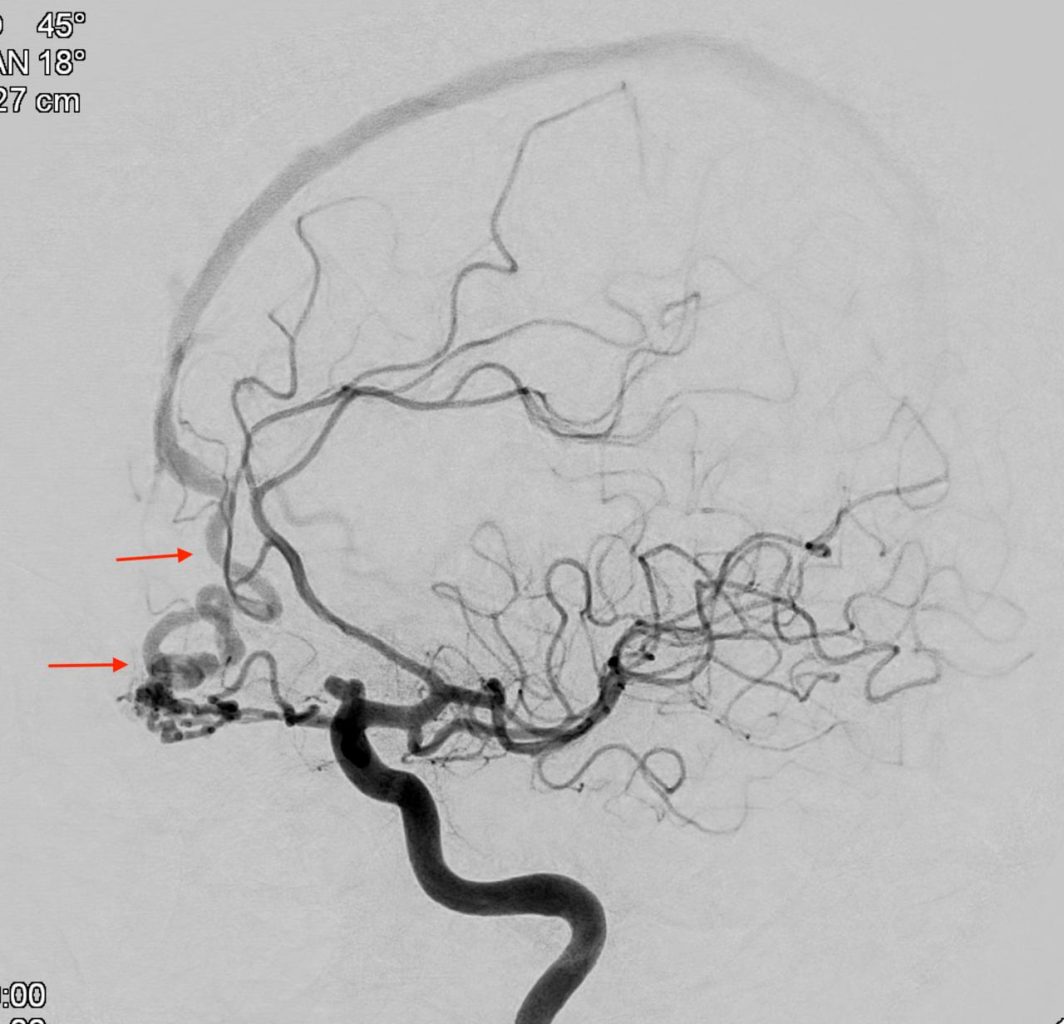

A angiografia cerebral é um exame que se destina a  diagnosticar patologias vasculares, e eventualmente tumorais, do cérebro e seus envoltórios e da cabeça e pescoço.

Um meio de contraste à base de iodo é injetado permitindo-se filmar e gravar a  circulação contraste pelos vasos arteriais e venosos.

A angiografia cerebral permite diagnosticar aneurismas cerebrais, malformações arteriovenosas, fistulas arteriovenosas piais ou durais, obstruções arteriais de diversas etiologias, sejam elas agudas (AVC) ou crônicas, vasculites (inflamações) dos vasos cerebrais, distúrbios da drenagem venosa do cérebro causando hipertensão intracraniana secundária, dentre outras patologias.

Este exame é invasivo e atualmente é realizado após outros exames menos invasivos, como a angiotomografia e angiorressonância, quando indicado.